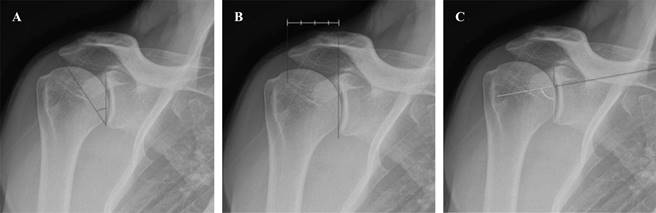

El ACH toma en cuenta indirectamente dos parámetros: la lateralidad acromial y la inclinación glenoidea, el aumento en la primera o una disminución en la segunda será considerado un factor de riesgo para el desarrollo de LMR.15 La inclinación glenoidea o ángulo beta (formado entre una línea que pasa por el borde superior e inferior de la glena y una que pasa por el suelo de la fosa supraespinosa) es el grado en que la glenoides se inclina hacia arriba en relación con la escápula. Un aumento de esta inclinación (disminución del ángulo), causa una traslación superior del húmero. La lateralidad acromial (distancia desde la glena hasta la parte más lateral del acromion) es la extensión lateral del acromion respecto a la glena y su aumento causa un mayor brazo de palanca sobre el deltoides (Figura 1).16

Figura 1: Radiografía anteroposterior verdadera de hombro (proyección de Grashey) en la que se mide: A) ángulo crítico del hombro, B) lateralidad acromial, C) inclinación glenoidea (ángulo beta).